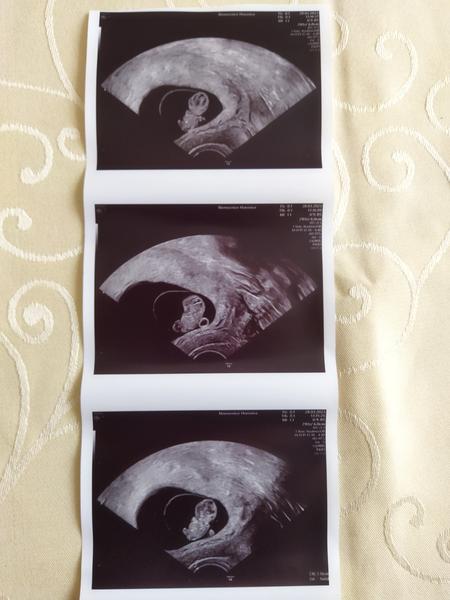

Holky tak jsme po kontrole,už máme 2,2 cm 😍🤣🤣 zahlédnuty mini ručičky, nožičky a hlavně srdíčko co bouchá😍😍 tatínek drobka z obrázků dojatý😉😉průkazku nemáme,ale PN díky rizikové práci a mému omdlívání vystavena, tak mohu být v klídku.Po Velikonočním pondělí náběry a pomalu se rozjede první screening,20.4.další ulltrazvuk😍Průkazku dostaneme až příště